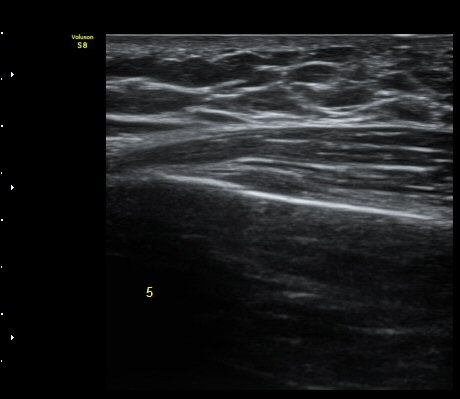

ÇÑ´Þ ÈÄ ÃßÀû°Ë»ç

Á¾´Ü¸é°Ë»ç¿¡¼­ °¡°ñ Çü¼ºÀÌ °üÂûµÊ(formation of callus)   »çÁø 3

°¥ºñ»À Ⱦ´Ü¸é°Ë»ç¿¡¼­ °¡°ñ Çü¼ºÀÌ °üÂûµÊ(formation of callus)  »çÁø 4